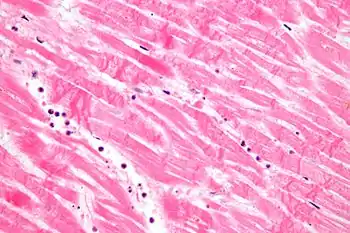

Under the microscope, myocardial infarction presents as a circumscribed area of ischemic, coagulative necrosis (cell death). On gross examination, the infarct is not identifiable within the first 12 hours.[20]

Although earlier changes can be discerned using electron microscopy, one of the earliest changes under a normal microscope are so-called wavy fibers.[21] Subsequently, the myocyte cytoplasm becomes more eosinophilic (pink) and the cells lose their transversal striations, with typical changes and eventually loss of the cell nucleus.[22] The interstitium at the margin of the infarcted area is initially infiltrated with neutrophils, then with lymphocytes and macrophages, who phagocytose ("eat") the myocyte debris. The necrotic area is surrounded and progressively invaded by granulation tissue, which will replace the infarct with a fibrous (collagenous) scar (which are typical steps in wound healing). The interstitial space (the space between cells outside of blood vessels) may be infiltrated with red blood cells.[20]

These features can be recognized in cases where the perfusion was not restored; reperfused infarcts can have other hallmarks, such as contraction band necrosis.[23]

| Stretched/wavy fibres | 1–2 h |  | ||

| Coagulative necrosis: cytoplasmic hypereosinophilia | 1–3 h | 1–3 days; cytoplasmic hypereosinophilia and loss of striations | > 3 days: disintegration |  |